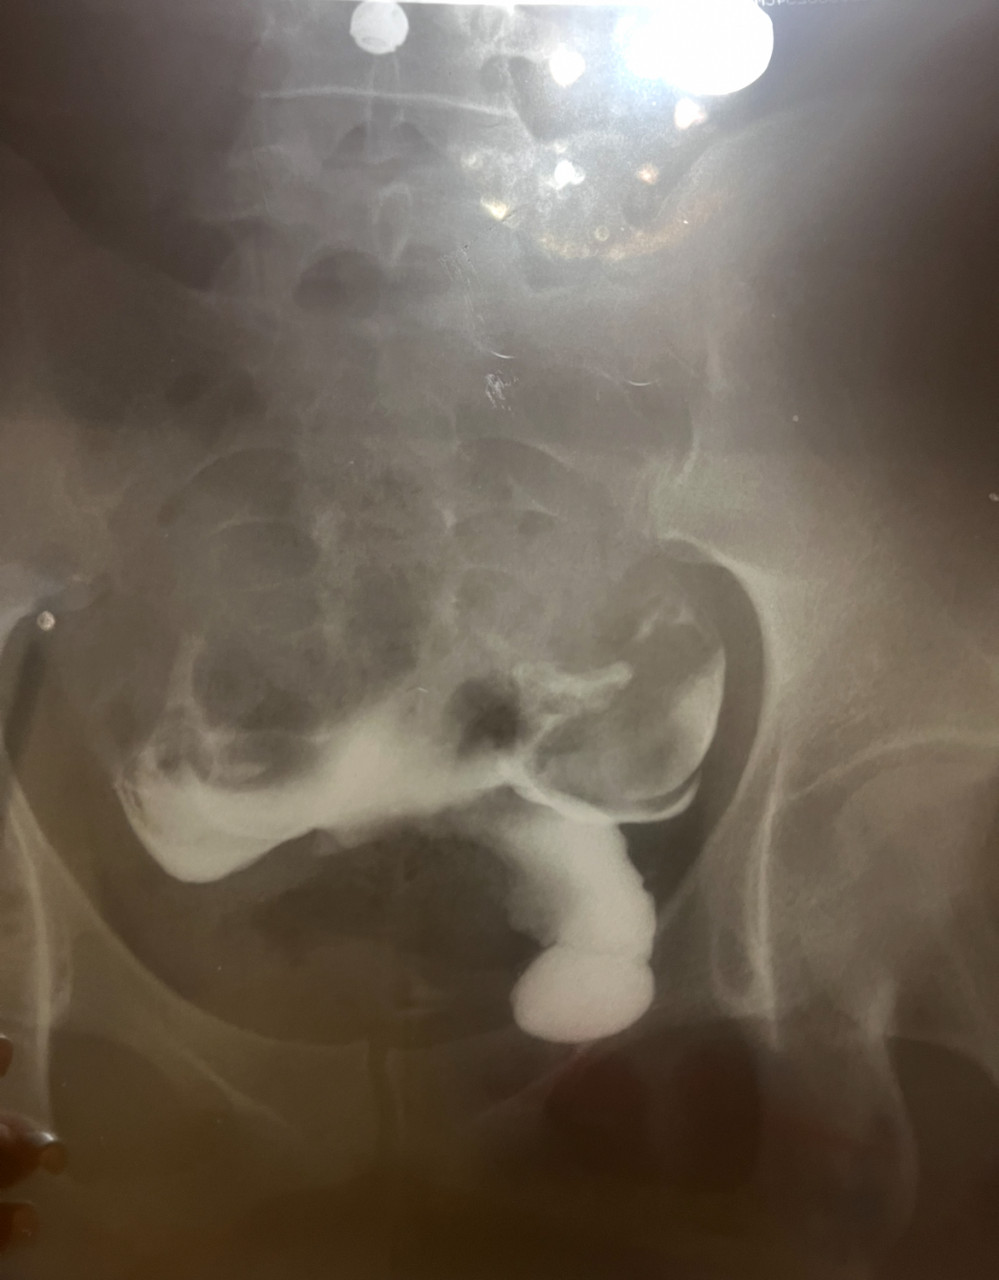

Здравствуйте. Помогите пожалуйста расшифровать снимок ГСГ маточных труб. Можно ли по нему сказать о проходимости или не проходимости маточных труб?

Здравствуйте. По представленным рентгеновским снимкам ГСГ контраст заполняет полость матки и проксимальные отделы маточных труб, но выхода контраста в брюшную полость, который указывает на проходимость труб, не видно. Это может говорить о неполной или полной непроходимости, однако для точного заключения нужно описание врача-рентгенолога проводившего исследование, так как оценка зависит от всех фаз исследования и качества снимков (вы предоставили фото снимков и может быть искажение).